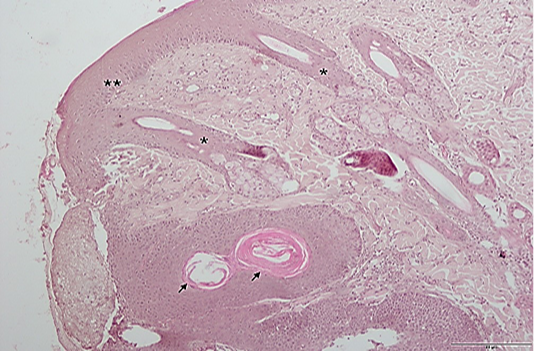

Figure 2

Histopathologic section of the excised tissue: rete accentuation (*), epidermal hyperplasia (**) and keratin pearl (arrow). (H&E, 10x). Scale; 5µm.